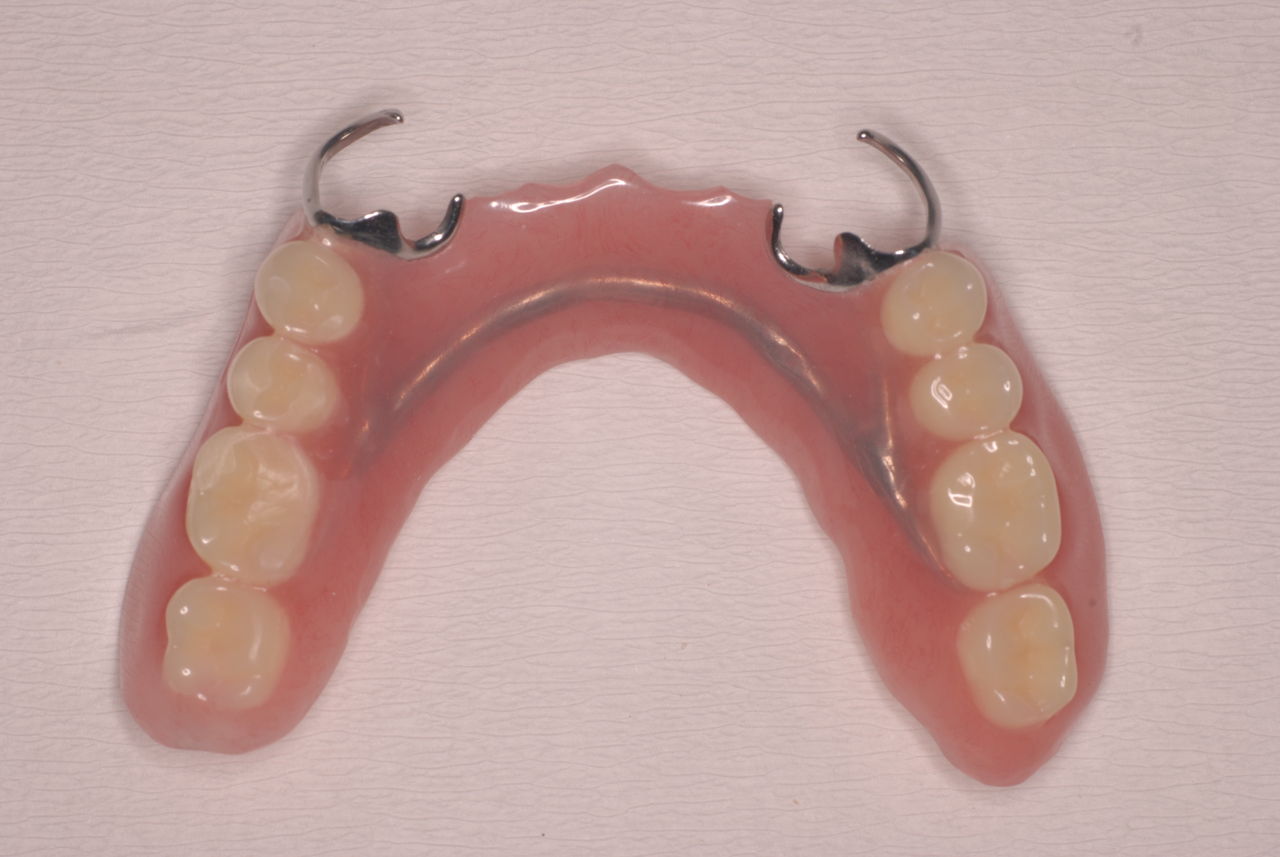

「川崎市の入れ歯なら新丸子西口歯科医院へ」

「神奈川県入れ歯・義歯センター・川崎市中原区新丸子の歯科医院 」